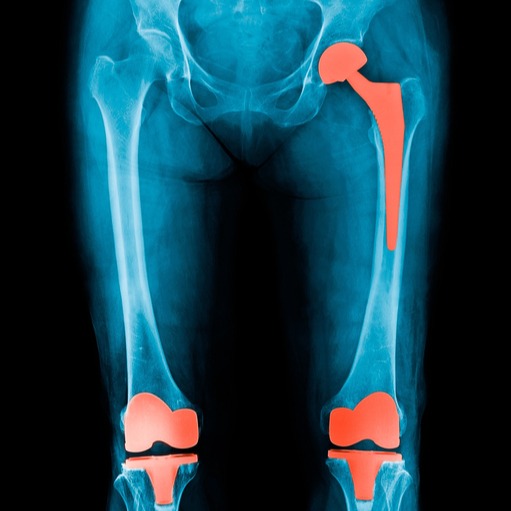

Nei casi più gravi, in cui sono presenti lesioni ossee di dimensioni medio-grandi, la procedura di elezione è chirurgica e consiste nella decompressione, in cui il tessuto danneggiato viene rimosso per stimolare la ricrescita di tessuto normale al suo posto. Infine, se il collasso osseo non è evitabile o è già avvenuto, la procedura di riferimento consiste nell’impianto di protesi articolari, generalmente protesi d’anca o di ginocchio

La fisioterapia può essere parte integrante del trattamento dell'osteonecrosi, specialmente nelle fasi avanzate della malattia o dopo interventi chirurgici, in quanto possono agevolare il recupero della mobilità e dei movimenti.